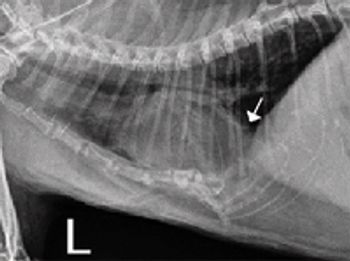

This condition often goes unnoticed for years, and many cases are discovered incidentally on radiographs.